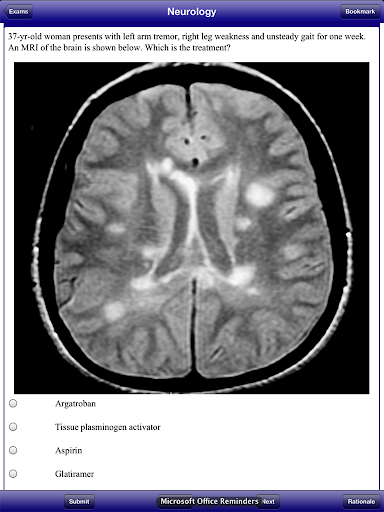

USMLE 2 Stanford Review Course, by David Nobel, MD, replicates the actual USMLE Step 2 Clinical Knowledge examination. USMLE 2 Stanford Review Course includes 1800 questions and answers written by trusted medical school professors who have reviewed the most recent USMLE 2 examination. USMLE 2 Stanford Review Course also includes 300 image format questions, including CT scans, MRIs, ECGs, and dermatology pictures.